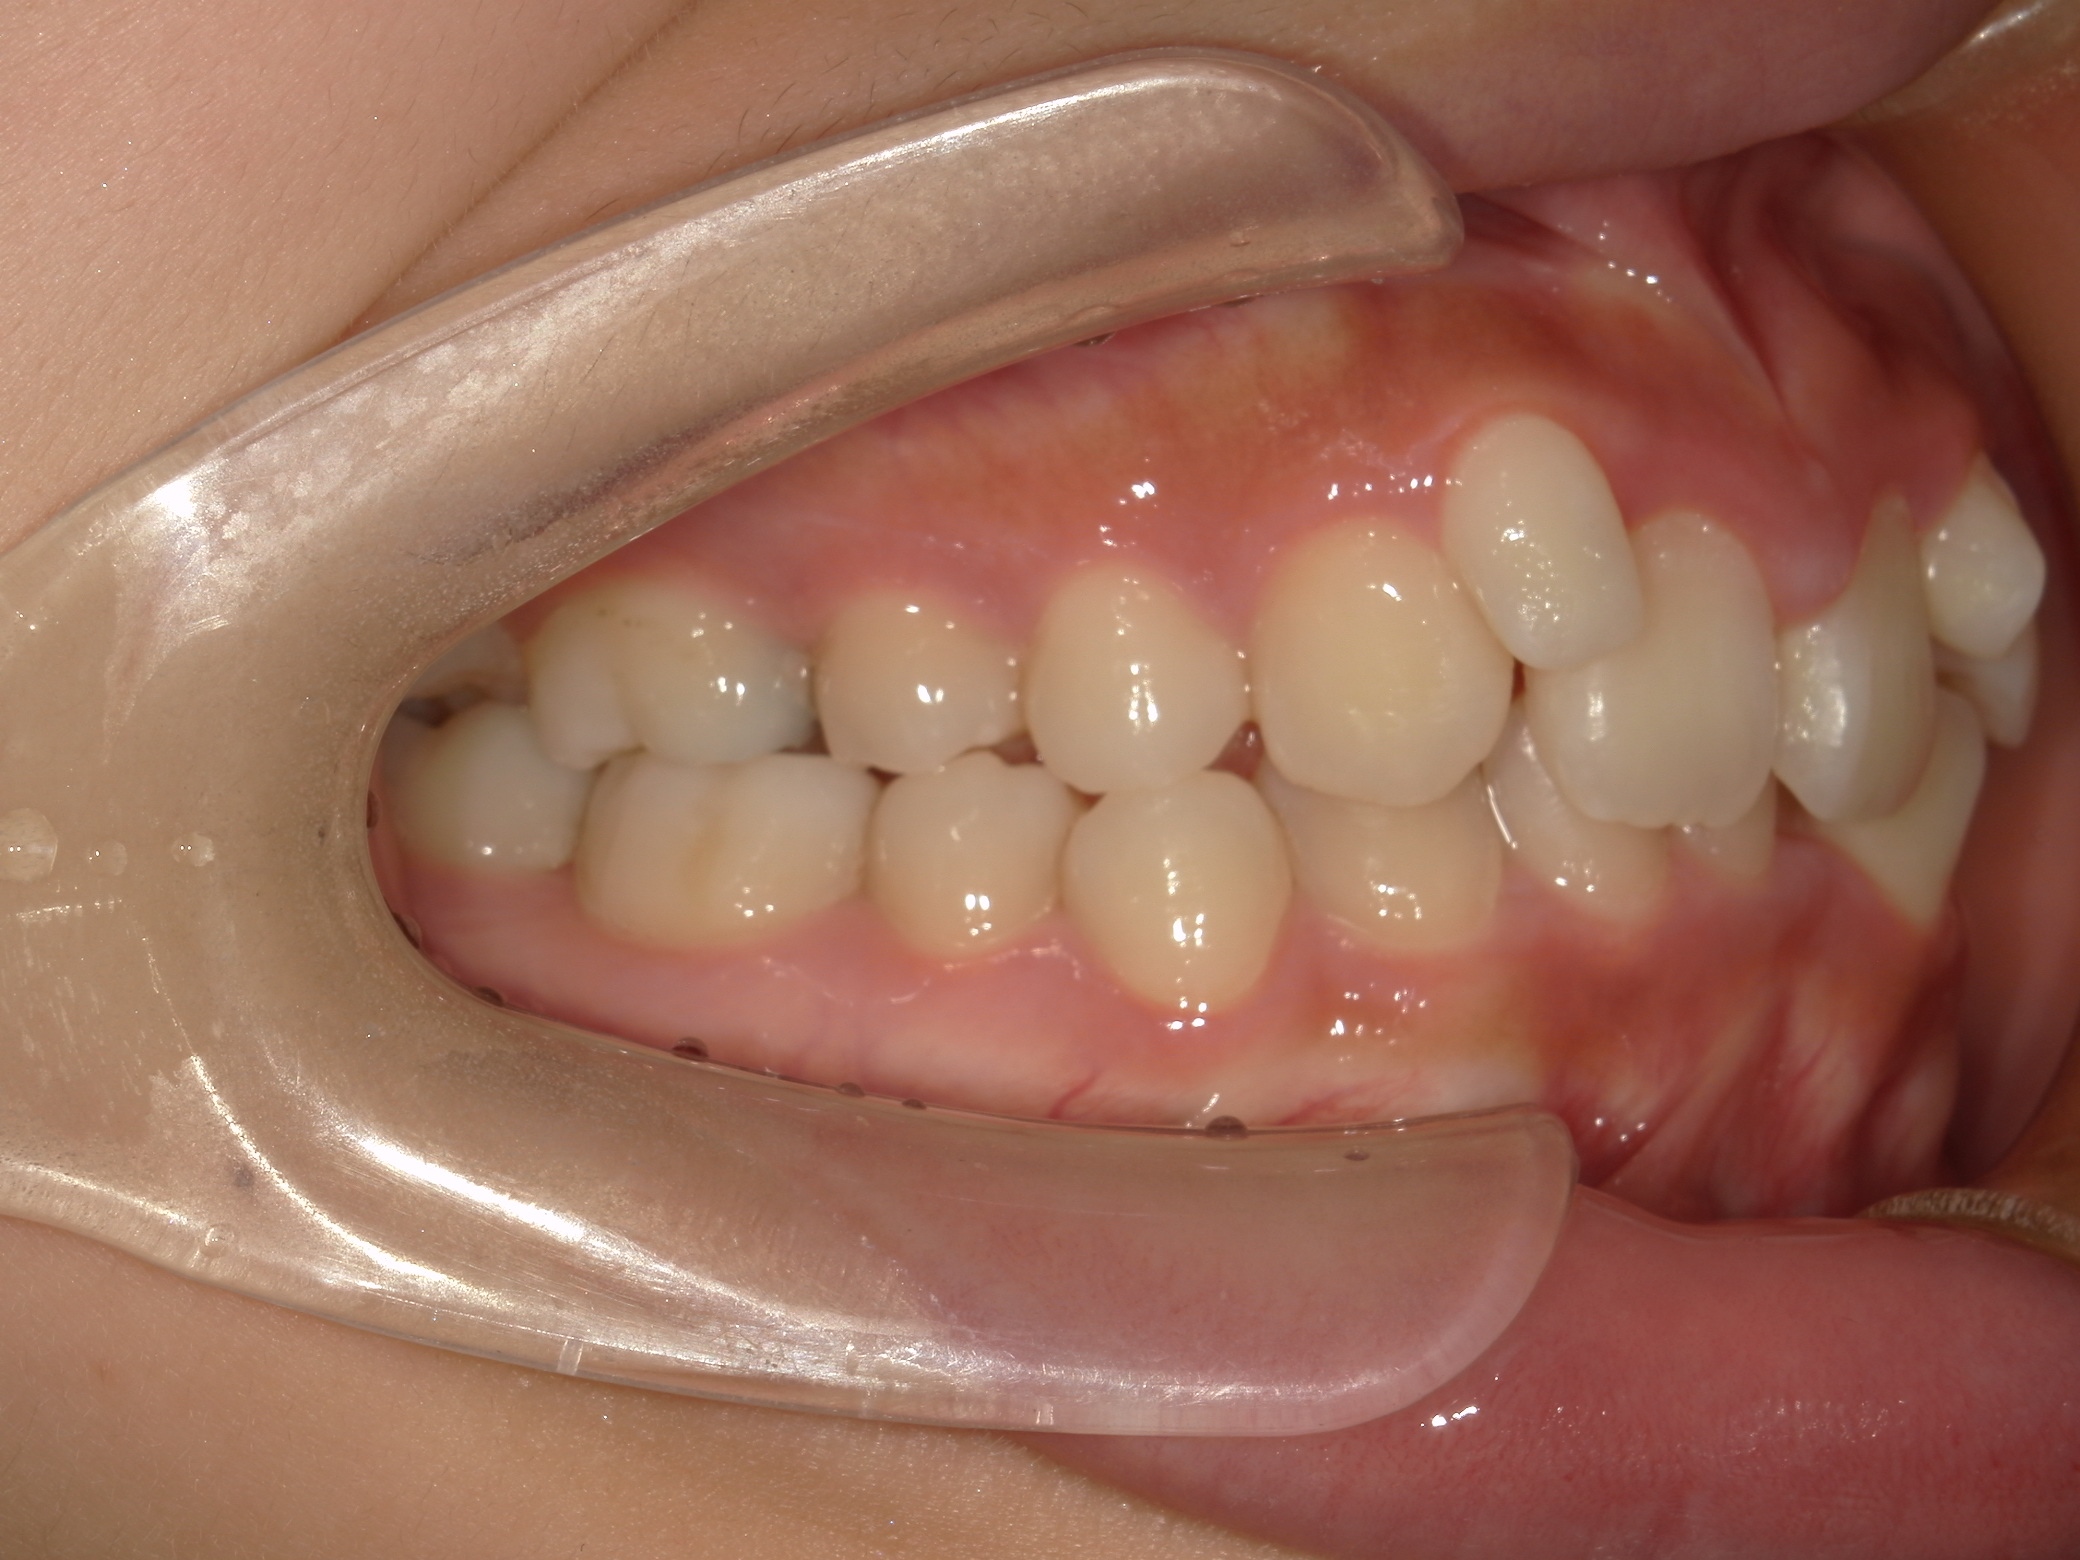

口内右

治療前

歯を並べる隙間を作るため、上下共に歯を抜いて治療を行うこととしました。

上は矮小歯を、下は横の歯を抜いて治療を行いました。

上の歯は2番の歯を犬歯で代替しているので、上下の大きさの違いが出るのですが、不自然にならないよう幅をわずかに調節して仕上げています。